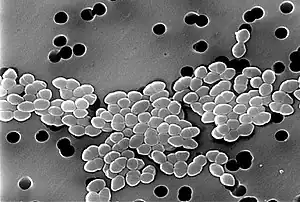

Linezolid is an antibiotic used for the treatment of infections caused by Gram-positive bacteria that are resistant to other antibiotics.[1][3] Linezolid is active against most Gram-positive bacteria that cause disease, including streptococci, vancomycin-resistant enterococci (VRE), and methicillin-resistant Staphylococcus aureus (MRSA).[3][4] The main uses are infections of the skin and pneumonia although it may be used for a variety of other infections including drug-resistant tuberculosis.[1][5] It is used either by injection into a vein or by mouth.[1]

Spectrum of activity

Linezolid is effective against all clinically important Gram-positive bacteria—those whose cell wall contains a thick layer of peptidoglycan and no outer membrane—notably Enterococcus faecium and Enterococcus faecalis (including vancomycin-resistant enterococci), Staphylococcus aureus (including methicillin-resistant Staphylococcus aureus, MRSA), Streptococcus agalactiae, Streptococcus pneumoniae, Streptococcus pyogenes, the viridans group streptococci, Listeria monocytogenes, and Corynebacterium species (the latter being among the most susceptible to linezolid, with minimum inhibitory concentrations routinely below 0.5 mg/L).[4][52][65] Linezolid is also highly active in vitro against several mycobacteria.[52] It appears to be very effective against Nocardia, but because of high cost and potentially serious adverse effects, authors have recommended that it be combined with other antibiotics or reserved for cases that have failed traditional treatment.[66]

Linezolid is considered bacteriostatic against most organisms—that is, it stops their growth and reproduction without actually killing them—but has some bactericidal (killing) activity against streptococci.[4][67] Some authors have noted that, despite its bacteriostatic effect in vitro, linezolid "behaves" as a bactericidal antibiotic in vivo because it inhibits the production of toxins by staphylococci and streptococci.[33] It also has a post-antibiotic effect lasting one to four hours for most bacteria, meaning that bacterial growth is temporarily suppressed even after the drug is discontinued.[21]